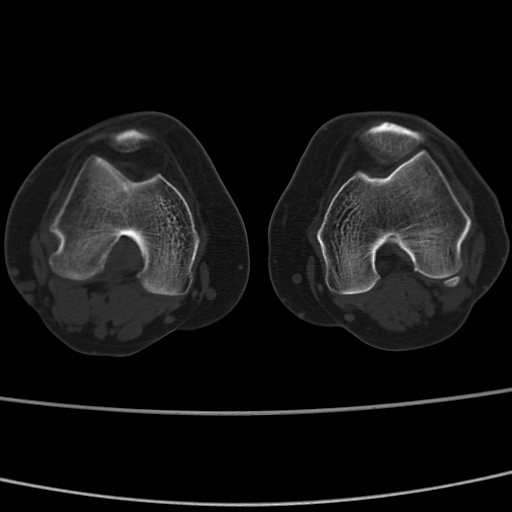

女性,50岁。【请提供患者临床症状体征】

右膝关节退行性改变,关节游离鼠。

右膝关节退行性改变,滑膜黏液囊钙/骨化并游离。

右膝关节退行性改变